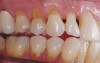

Replacement of existing restorations is responsible for 75% of all operative dentistry.15,19 The reasons for placement and replacement of restorations of direct restorative materials include: primary caries (Figure 1 and Figure 2); recurrent caries (Figure 3); poor margins (Figure 4 and Figure 5); restoration fracture (Figure 6 and Figure 7); tooth fracture (Figure 8); esthetics (Figure 9); non-carious tooth structure lost (attrition, abrasion, abfraction, erosion) (Figure 10); and pain/sensitivity.

Fig. 1 Initial caries. Class V carious lesions.

Figure 1  Initial caries. Class V carious lesions.

Figure 1